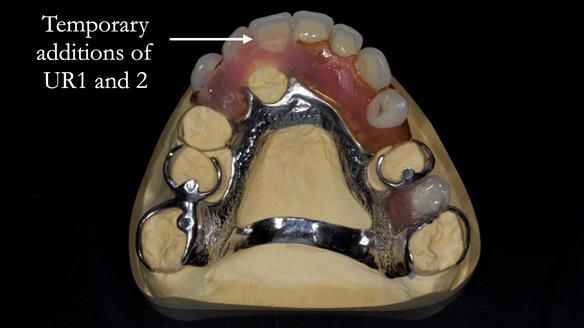

- Add upper right lateral and central incisor denture teeth to existing upper RPD as temporary measure during making of new RPDs

- New metal based upper and lower RPDs of Scandinavian design for improved, periodontal health, function and appearance.